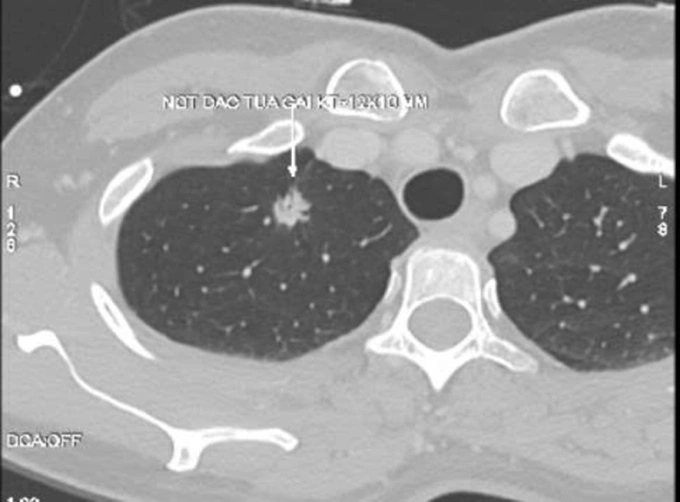

Kết quả chụp CT tại Bệnh viện Đa khoa Tâm Anh Hà Nội cho thấy phổi phải của bà Liên có nốt đặc tua gai, kích thước khoảng 12×10 mm, xếp loại Lung-RADS 4X. TS.BS Vũ Hữu Khiêm, Trưởng khoa Ung bướu, giải thích 4X là phân loại cao nhất trong hệ thống Lung-RADS, cho thấy tổn thương có đặc điểm hình ảnh bất thường, nguy cơ ác tính cao.

Nốt phổi nguy cơ cao của bà Liên trên phim chụp CT. Ảnh: Bệnh viện Đa khoa Tâm Anh